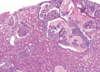

Gross pathologic features of Wilms tumor?

Nodular

Gray to tan-white

Soft, friable, fleshy

Wilms tumor Microscopic features (3)

- Triphasic pattern*

- Primitive blastema (small/dark undifferentiated cells)

- Epithelial component (abortive tubules/glomeruli)

- Stroma (Fibrous or myxoid patterns; may contain mesenchymal elements (cartilage, muscle, bone)

Wilms tumor microscopic features (3):

Triphasic pattern

- Primitive blastema (small/dark undifferentiated cells)

- Epithelial component (abortive tubules/glomeruli)

- Stroma (Fibrous or myxoid patterns; may contain mesenchymal elements (cartilage, muscle, bone)